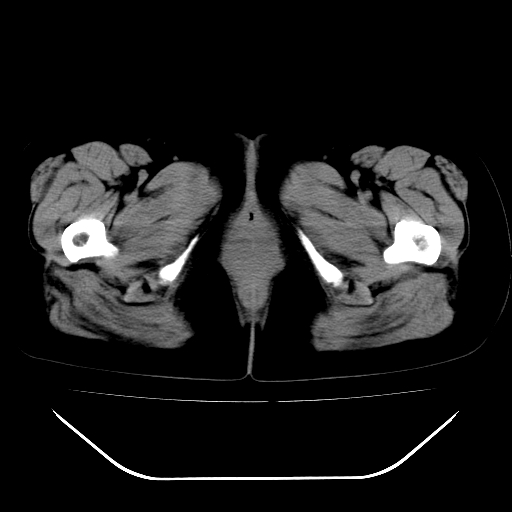

女,48岁,肛门坠胀感一年,肠镜未见异常。

子宫明显增大,形态不规则。多考虑:子宫肌瘤!

子宫明显增大,形态不规则,  盆腔积液 结合临床考虑:1子宫肌瘤, 2  盆腔炎。

道格拉斯窝积液考虑慢性盆腔炎,宫腔少量积液,子宫肌瘤不好说,建议增强。